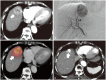

Yttrium-90 transarterial radioembolization (TARE) has emerged as a valuable treatment option for hepatocellular carcinoma (HCC) and is being increasingly incorporated into clinical guidelines. Recent advancements in dosimetry, including personalized dosimetry and multi-compartment modeling, have significantly improved tumor response and clinical outcomes. Although high tumor-absorbed doses are associated with better oncologic control, careful dose adjustment is essential for minimizing toxicity to normal liver tissue and lungs. This review explores the key aspects of TARE dosimetry, including single- and multi-compartment modeling, differences between resin and glass microspheres, dose-response relationships, and strategies to mitigate hepatotoxicity and radiation pneumonitis. Various clinical applications of TARE have been discussed, ranging from curative-intent radiation segmentectomy and lobectomy to palliative treatment of diffuse and macrovascular invasion-associated HCCs. In South Korea, where cadaveric liver transplantation is limited, a multidisciplinary approach is particularly important for optimizing treatment strategies and preserving liver function for potential future interventions. As dosimetry continues to evolve, further research is required to refine dose optimization protocols and validate their clinical impact in different patient populations, including those in South Korea.